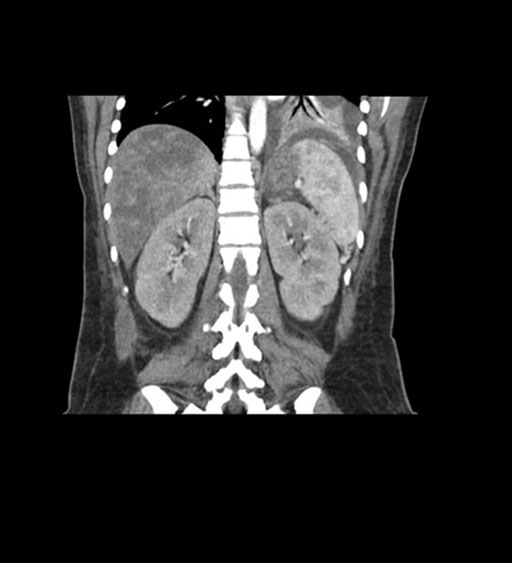

Coronal Arterial

Coronal Venous

Imaging analysis

Based on initial findings, which issue(s) would you be most concerned about?